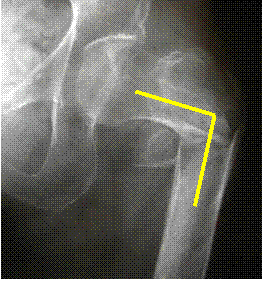

There is a

comminuted

femoral fracture

with varus

angulation

Varus= distal fragment

points toward body